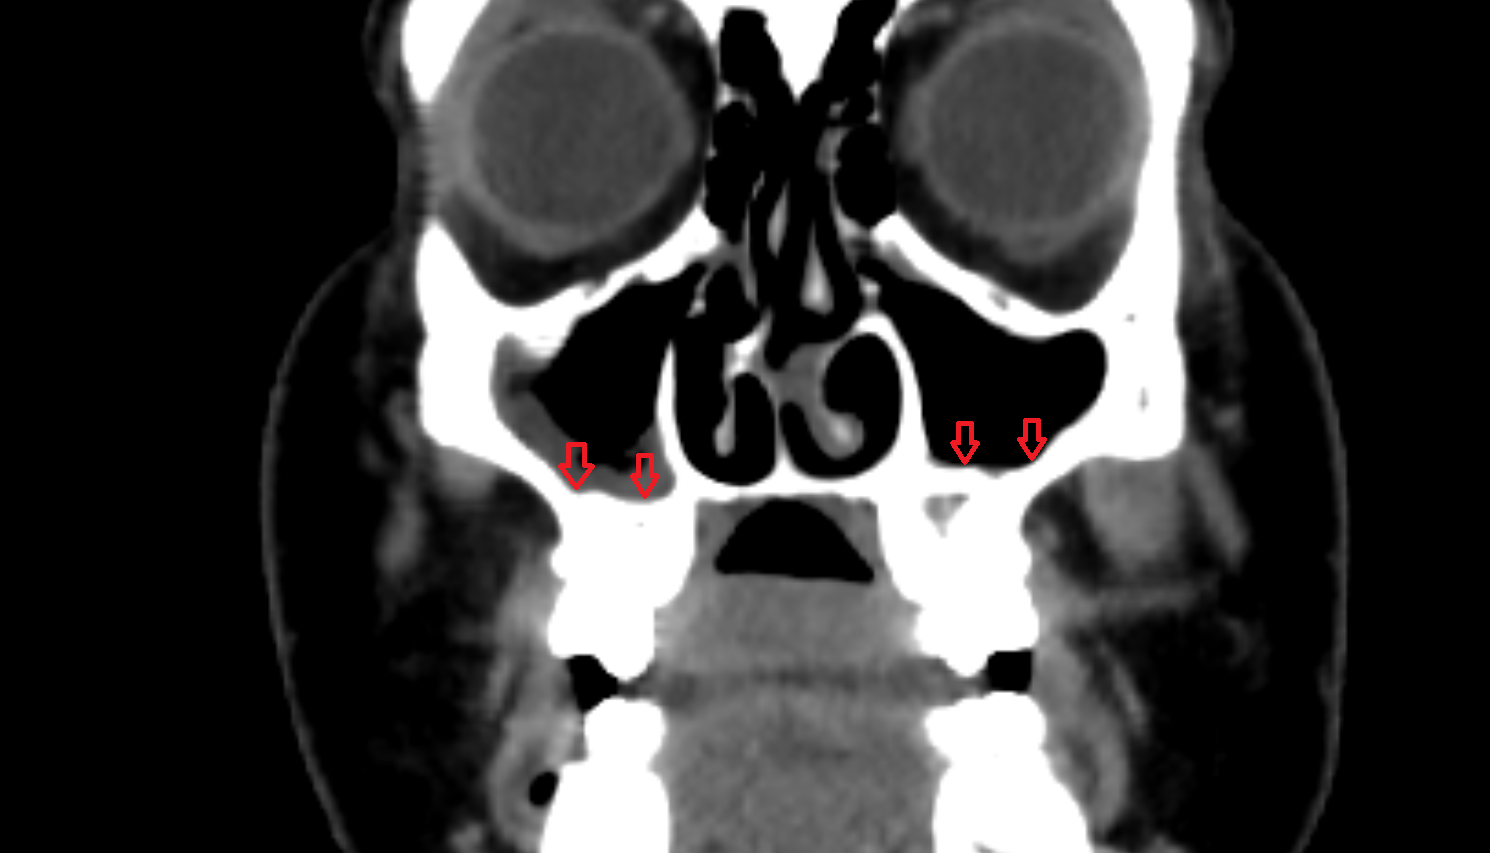

- Maxillary sinus